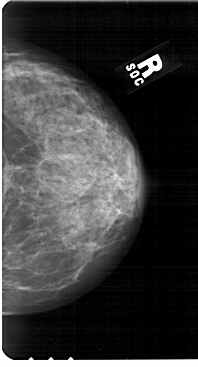

A_1851_1.RIGHT_MLO

RIGHT_MLO LINES 5491 PIXELS_PER_LINE 3091 BITS_PER_PIXEL 12 RESOLUTION 43.5 NON_OVERLAY